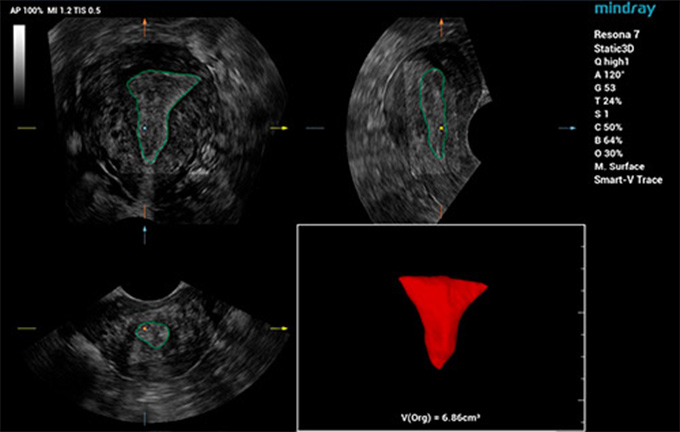

针对胎儿颅脑、面部、脊柱、长骨这类具备3D特性化的操作的临床应用场景,仁合创新开发了场景化自动容积扫描,只需“一键”即可完成自动场景识别、自动成像及优化、自动切面获取、自动定量分析,真正实现了贯穿整个检查流程的自动化工作流,降低诊断对操作者的依赖性,轻松提升病人检查效率。